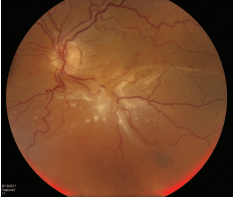

Intraocular Melanoma

Malignant intraocular melanoma is the most common eye cancer in adults. The tumor affects the uveal tract, which is the middle layer of the wall of the eye.

CAUSES

During a targeted tumor examination, diagnostic testing typically includes a complete eye exam with dilation of the fundus, indirect ophthalmoscopy, tumor photography (fundus photography), tumor ultrasound, and vascular studies of the tumor (fluorescein angiography, indocyanine green angiography, spectral-domain OCT angiography (sd OCT)), along with laser studies of the macula.

SYMPTOMS

Tumor sizing Typically, ocular oncologists use 5 categories for tumor sizing: small, medium, large, extra-large, and a fifth category for borderline small tumors called atypical nevi (singular: nevus). Tumor sizing is important, as it has an impact on treatment options for the patient.